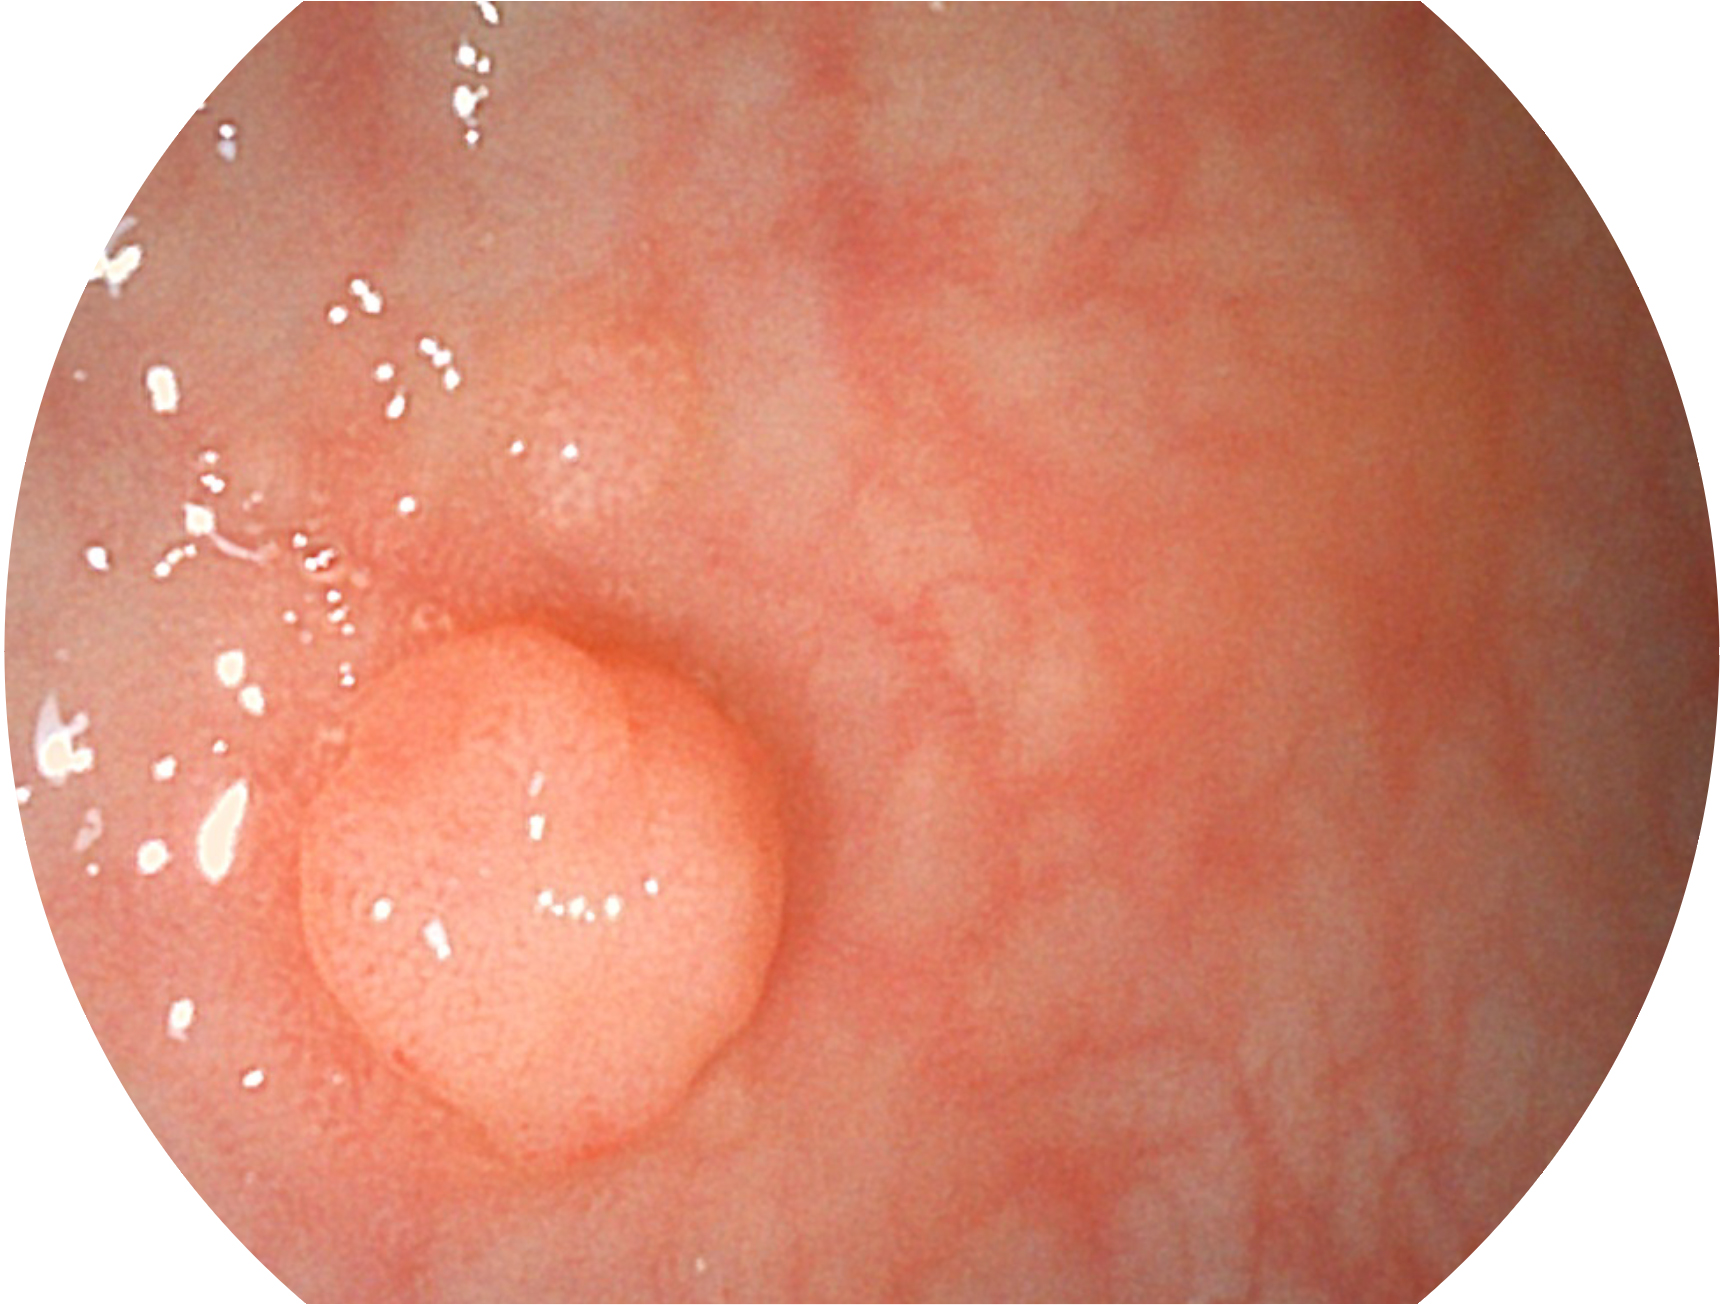

16877太阳集团新开发的内镜染色技术,主要是基于多波长LED 光源的开发,VLS-55Q 四波长LED 光源是由四个不同颜色的LED光按照相应照明模式所规定的特定发光比例进行合束后形成,合束后形成的照明光的光谱由红光、绿光、蓝光及蓝紫光这四个不同的波段范围构成。具有更高光谱自由度,通过光谱比例的控制,实现了聚谱成像技术,英文全称为“Spectral Focused Imaging, SFI”,缩写为“SFI”和光电复合染色成像技术,英文全称为“Versatile Intelligent Staining Technology, VIST”,缩写为“VIST”。